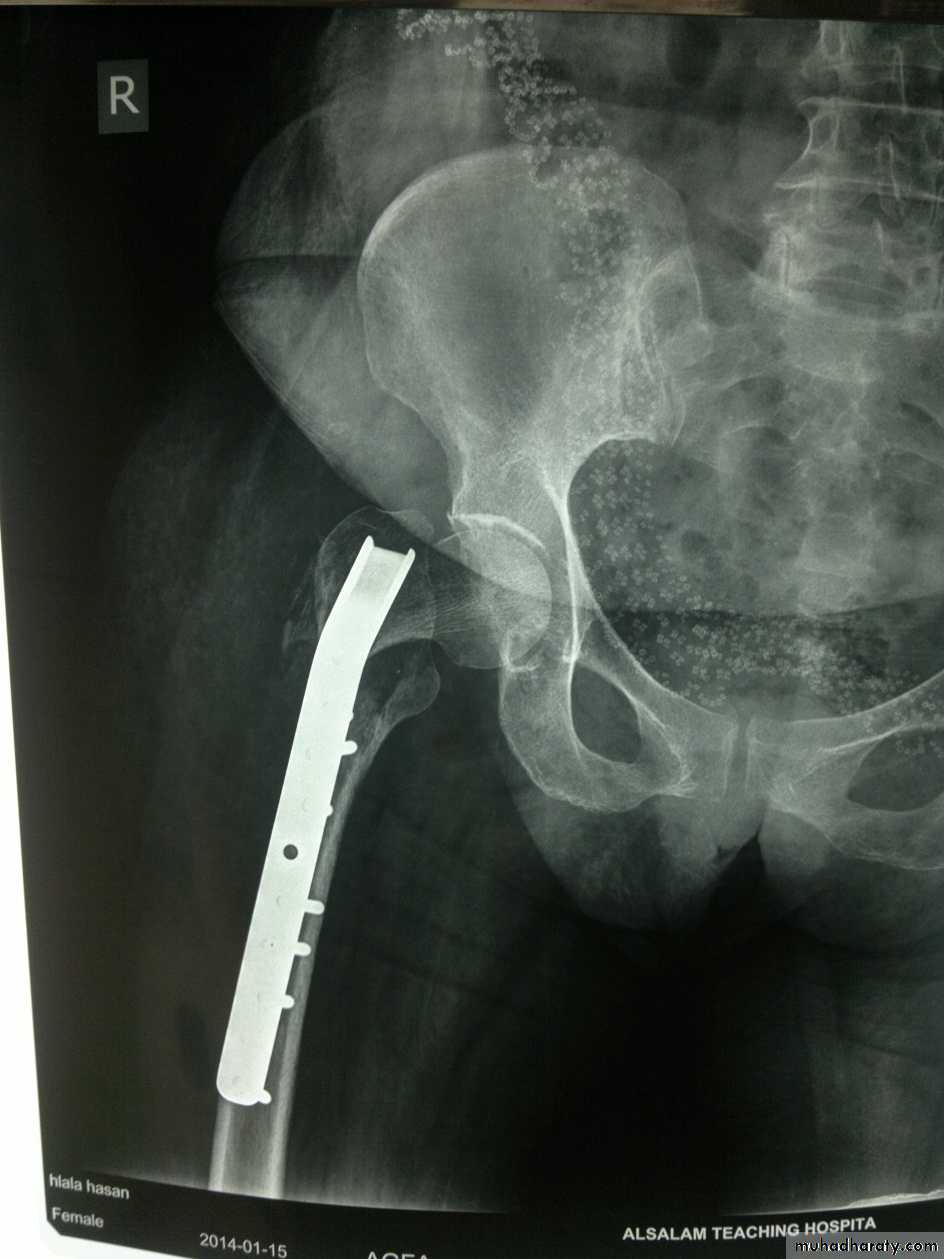

The fracture is fixed with an angled device – preferably a sliding screw in conjunction with a plate (dynamic hip screw) or

intramedullary nail. or

95 degree screw-plate (L-Plate)

Dynamic hip screw

L-plate (fixed angle plate)